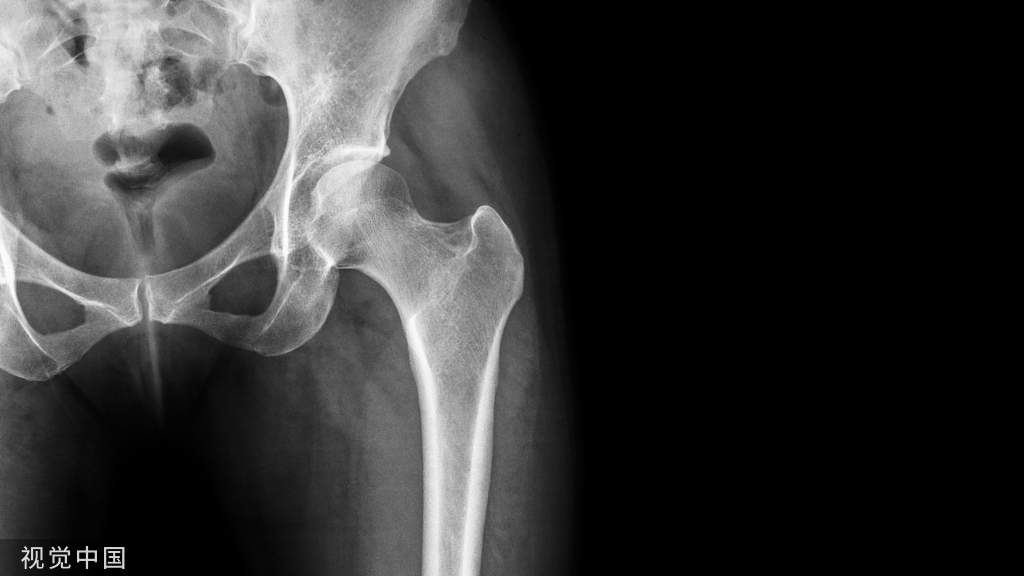

关节穿刺抽出液体多为黄色,清澈,或有血液而呈粉红色,细菌培养阴性。X线检查滑膜炎骨质无异常,或者有退行性改变,或者有关节内游离体,骨关节边缘有骨刺。

X线检查,创伤性膝关节滑膜炎骨质多无异常,或者有退行性改变,或者有关节内游离体。关节积液量多可见关节囊膨胀影。

膝关节软组织肿胀,髌下脂肪垫消失